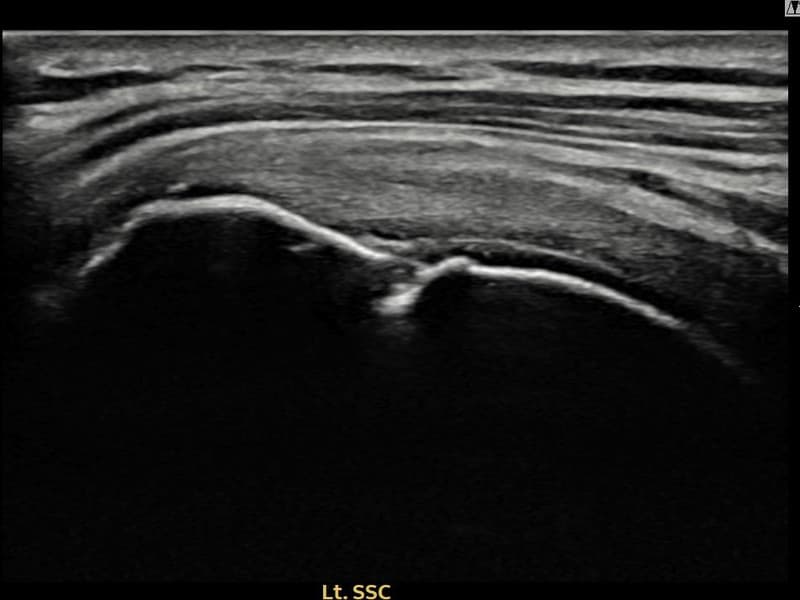

术后

术前超声确认左侧 冈上肌腱 附着部部分撕裂,左侧冈上肌腱回声不连续伴肌腱缺损(11mm × 4mm (肌腱厚度约44%缺损))。术后超声显示撕裂部位充满再生组织,肌腱连续性恢复,回声模式正常化。